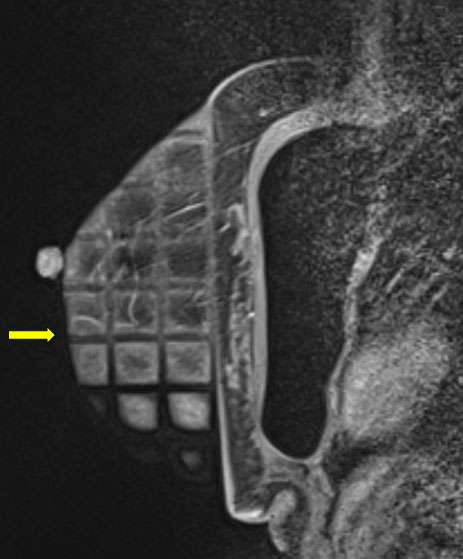

• Obtain images of the breast pre-contrast administration (fig 1) (sequences used can vary depending on institutional preferences)

Procedure: MR Guided Breast Biopsy Figure 1

Figure 1. Sagittal T1-weighted fat saturated pre contrast images demonstrate a biopsy grid overlying the lateral breast in compression. In this patient with silicone implants, the implant must be excluded during compression.